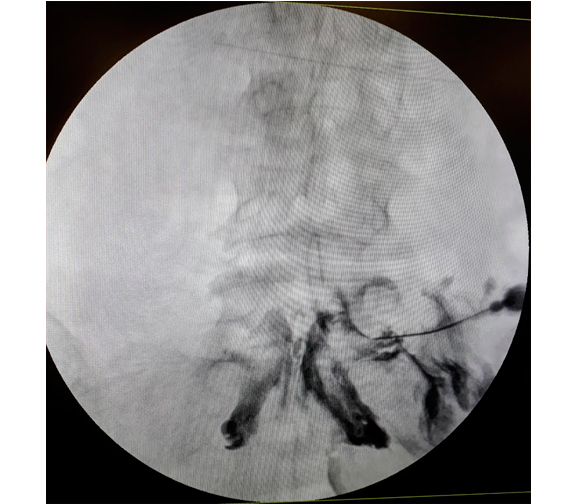

Un bloqueo epidural de esteroides es un procedimiento mínimamente invasivo cuya finalidad es ayudar a aliviar el dolor de cuello, brazo, espalda y piernas causado por nervios espinales inflamados debido a estenosis espinal o hernia discal. El medicamento va directo al espacio epidural.

El alivio del dolor puede durar varios días o incluso años. Lograr reducir el dolor para que pueda reanudar las actividades normales y un programa de fisioterapia.